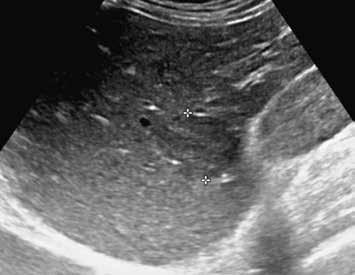

V UZ jsou patrná vícečetná izoechogenní ložiska (1, 2). U jiného pacienta (3) vidíme v játrech převážně hypoechogenní ložiska (žluté šipky) s naznačeným hyperechogenním periferním lemem (červené šipky). Po aplikaci kontrastní látky se ložiska patrná na obr. 1, 2 homogenně sytí a ani téměř po třech minutách nedochází k jejich vymývání (4–6).

Ultrazvukový obraz ukazuje většinou homogenní, někdy lobulované ložisko. V 60 % je hypoechogenní (obr. 1, 2), může však být izoechogenní nebo mírně hyperechogenní (obr. 3) vzhledem k normálnímu jaternímu parenchymu. Častěji se FNH vyskytuje v terénu steatotických jater. Ve 20 % případů nacházíme centrální jizvu.

V pravém laloku jater jsou na UZ lehce hypoechogenní ložiska s naznačeným výrazně hypoechogenním lemem (1, 2).